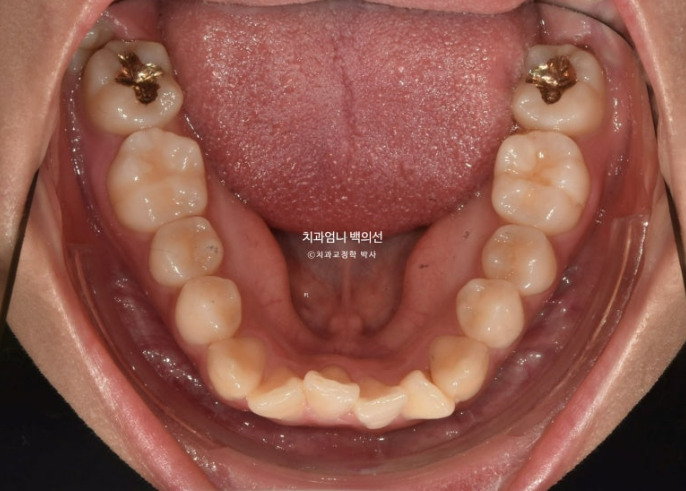

아래 앞니가 많이 삐뚭니다.

부분교정에서는 앞니 배열될 공간을 소량의 치간삭제로 얻습니다.

앞니 부분교정용 장치 중 MTA 장치를 선택하셨고 치료에 들어갔습니다.

MTA 장치는 송곳니부터 송곳니까지 앞니에만 붙여서 배열을 진행했고 나머지 작은어금니와 큰어금니는 움직이지 않았습니다